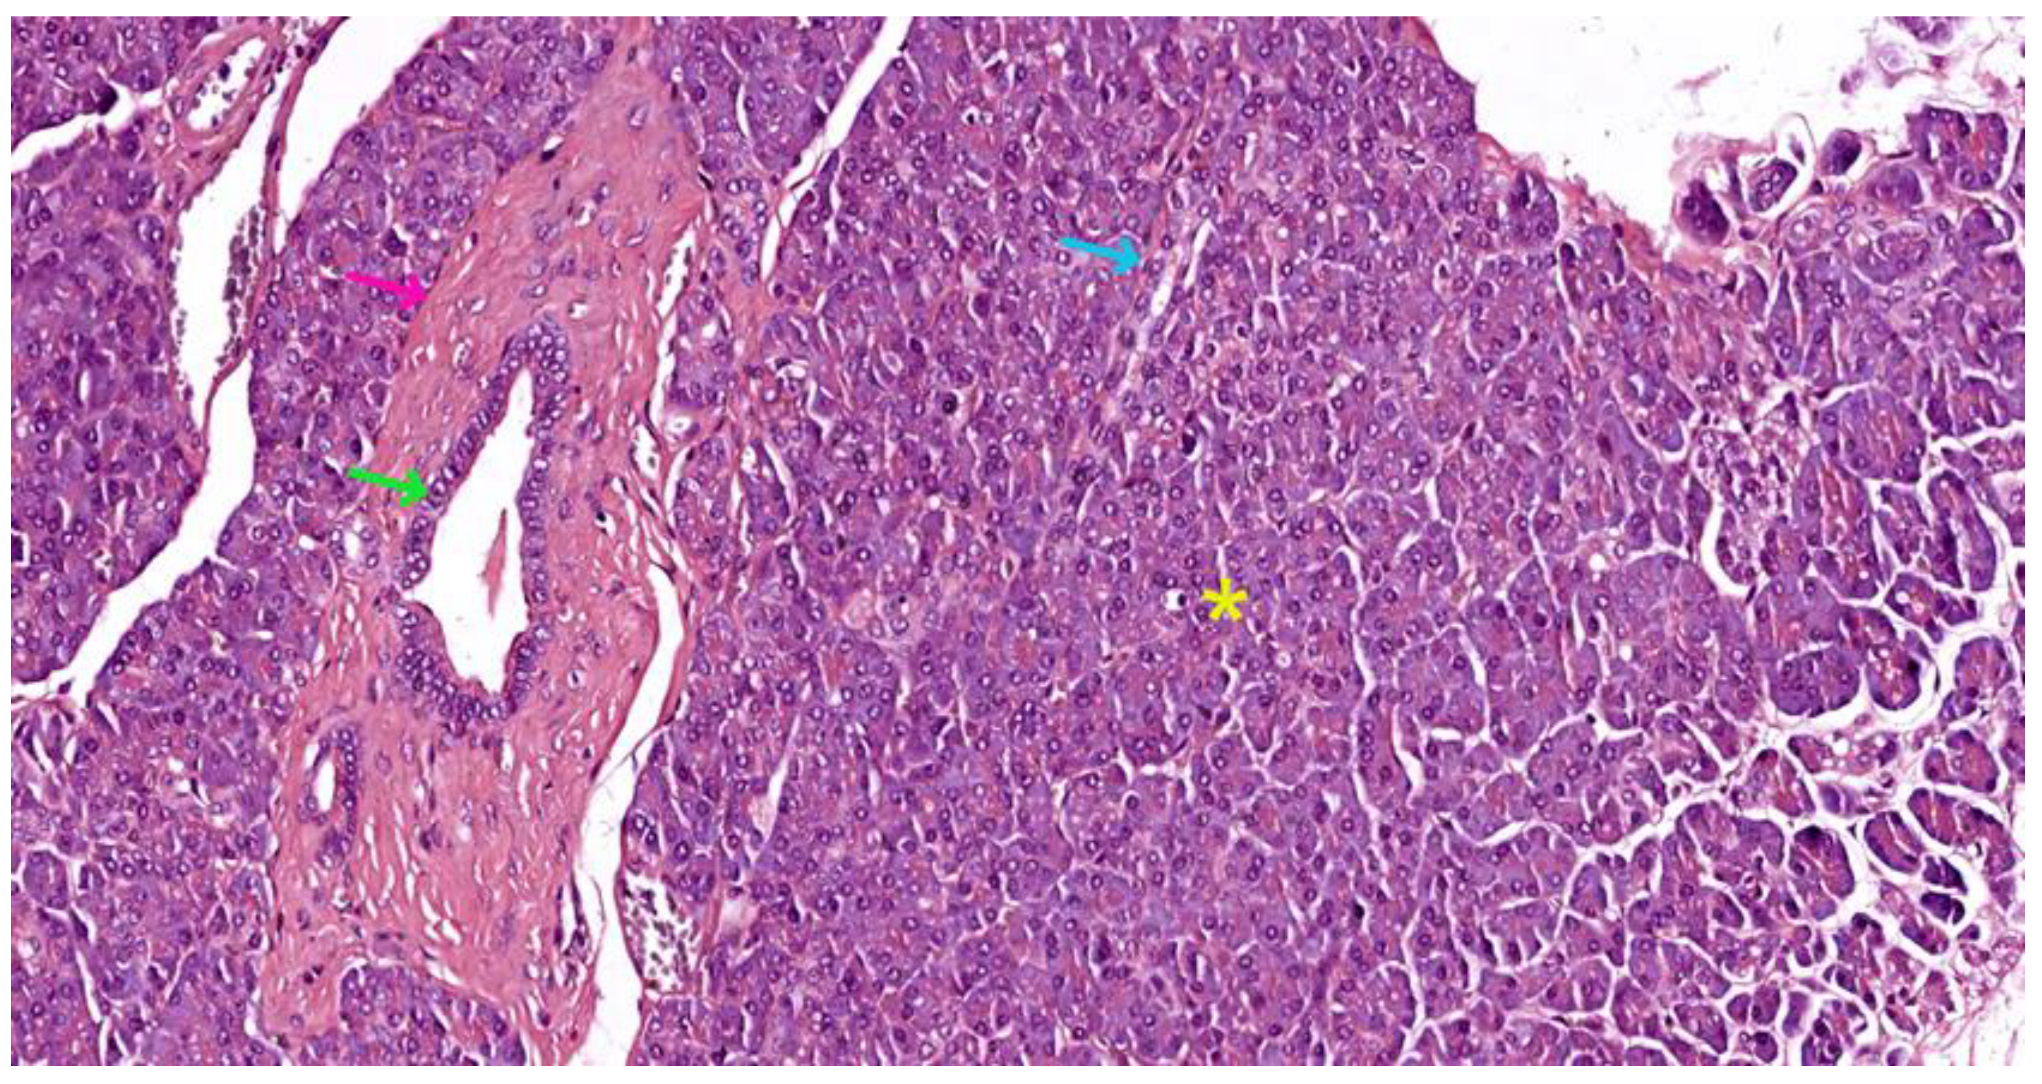

- Inter-lobular ducts - located in connective trabeculae; they have a wide lumen and are delimited by simple columnar epithelium; they are surrounded by well-represented dense irregular connective tissue, which contains fibroblasts and myofibroblasts (see Figure 5);